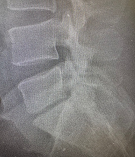

Пациент П., 05.05.2025 г. при взрыве снаряда получил слепое проникающее в позвоночный канал осколочное ранение пояснично-крестцового отдела позвоночника. В течение двух месяцев пациенту оказывалось консервативное лечение. 13.07.2025 г. пациент поступил на лечение в ГВКГ им. ак. Н.Н. Бурденко. При обследовании на КТ выявлен осколок металлической плотности в межтеловом промежутке по срединной линии у заднего края тел на уровне пятого поясничного и первого крестцового позвонков. Осколок прошел через междужковый промежуток сзади по краю фасеточного сустава. У больного имелась клиника болевого синдрома в пояснично-крестцовом отделе позвоночника во время движений и парестезий в проекции S1 корешка. Силовых расстройств не было.

Рис. 1 КТ-картина расположения осколка в трех проекциях.